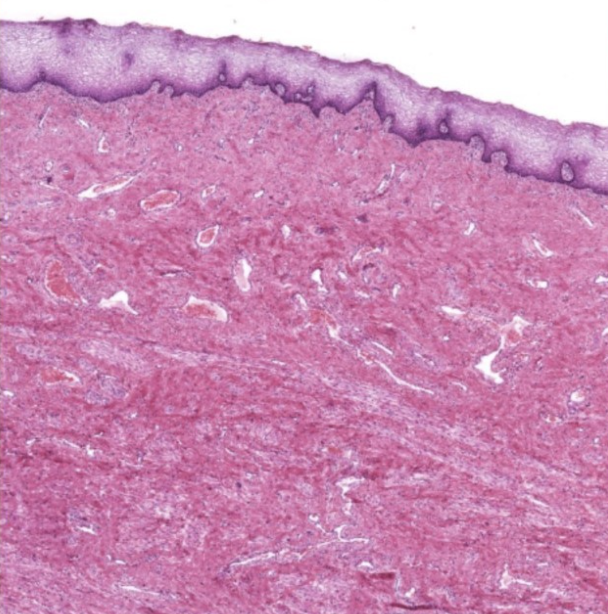

vagina epithelium

stratified squamous non keratinized epithelium and lamina propria

vagina muscularis

indistinct thin inner circular and thick outer longitudinal layer

layers of vagina

mucosa, muscularis, adventitia